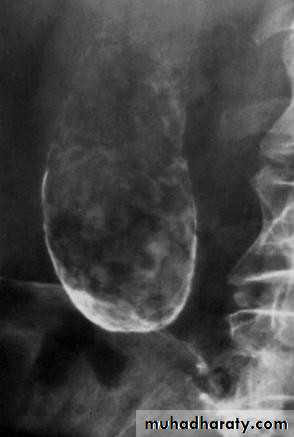

•  Plain radiogaph:

•  Radiopaque gall stones in 10%

•  Porcelain GB.. calcified GB..25% CA.

• Porcelain GB